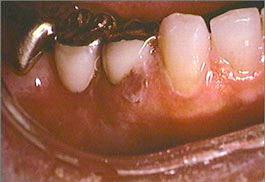

The skin on the right side of the face is erythematous and contains small vesicles and ulcers. Small ulcers are present on the right dorsum of the tongue, mucobuccal fold and the gingival papilla between the mandibular right central and lateral incisors. The mandibular right first and second molars and the surrounding mucosa are painful to palpation. The periapical radiograph reveals no evidence of periapical disease. The mandibular right first and second molars are responsive to pulp testing and give no evidence of pulpitis. No palpable lymph nodes are present.

mandibular anterior teeth and gingiva right mandibular teeth and mucobuccal fold

close-up of right mandibular teeth and gingiva